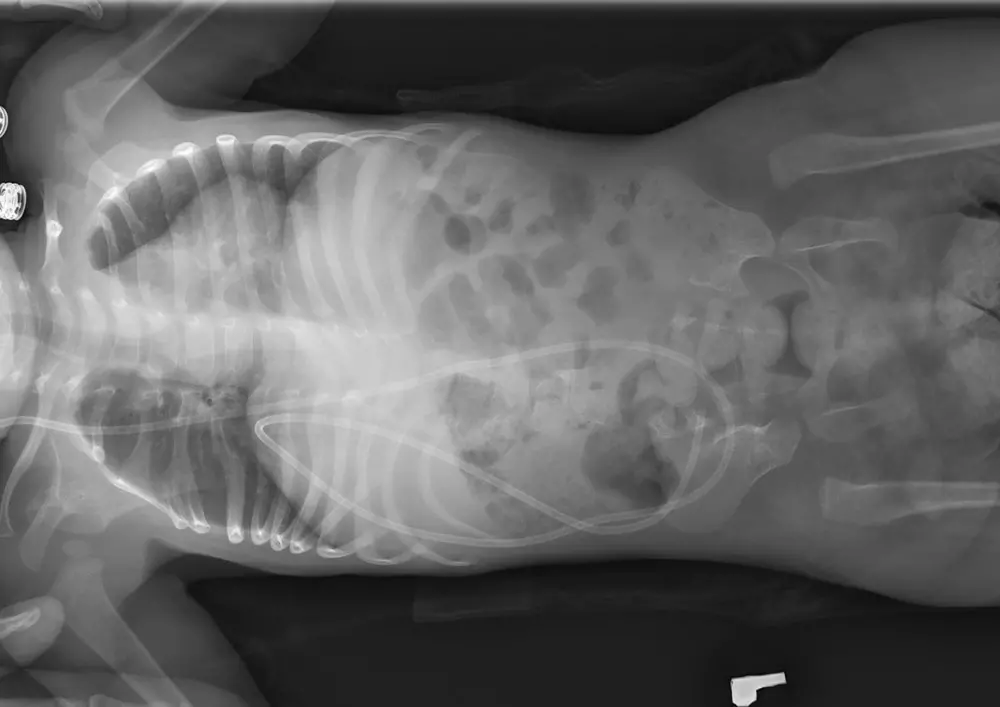

Metoda Vojty w leczeniu przepukliny oponowo-rdzeniowej

W dziale „Nowoczesne metody fizjoterapii” znajdą Państwo tekst pt. „Metoda Vojty w leczeniu przepukliny oponowo-rdzeniowej”. Mgr Ewa Żulewska-Fiks wskazuje, jak ważne jest przeprowadzenie operacji w ciągu pierwszych 72 h życia dziecka. Pomaga to uniknąć infekcji, przywrócić prawidłowe krążenie płynu mózgowo-rdzeniowego, zabezpieczyć rdzeń i otaczające go tkanki przed urazem. To również krok ku szybszemu usprawnianiu ruchowemu dziecka. Metoda Vojty jest polecana ze względu na wszechstronność, skuteczność oraz niewielki koszt leczenia z jej wykorzystaniem.